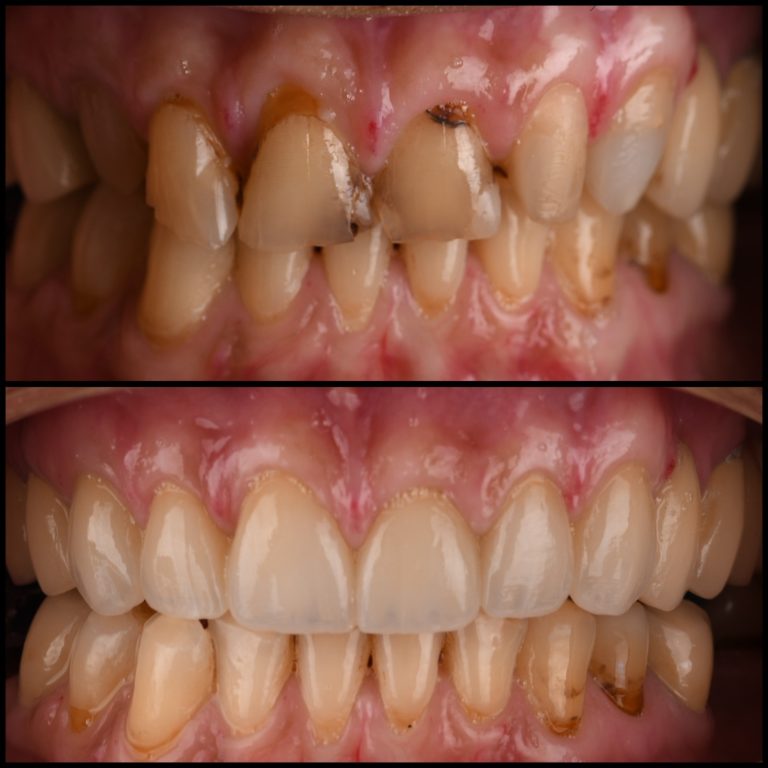

Naša protetska usluga omogućava vam potpunu transformaciju osmeha. Bilo da su vam potrebne fasete, mostovi, krunice, parcijalne ili totalne proteze, naš stručni tim posvećen je vraćanju funkcionalnosti i estetike vašem osmehu. Pored analognog načina uzimanja otiska koristimo I savremeni skener, koji pruža veću udobnost i brzinu. Skener omogućava precizno snimanje vaših zuba i usne duplje, olakšava komunikaciju sa tehnikom i omogućava pacijentu da aktivno učestvuje u planiranju i sagledavanju opcija u “digital smile designed” programu vodeći ka predvidivim rezultatima. Korišćenjem visokokvalitetnih materijala i preciznih tehnika u izradi protetskih radova,

obezbeđujemo prirodan izgled vaših novih zuba.

krunice su protetski nadoknade koje preuzimaju funkciju oštećenih ili izgubljenih prirodnih zuba. Služe kao zamena za zube koji su znatno oštećeni ili u potpunosti nedostaju. Savremena stomatologija omogućava izradu krunica koje deluju potpuno prirodno, a istovremeno su veoma izdržljive. Mogu se nijansirati tako da se savršeno uklope u postojeći niz zuba ili doprinesu stvaranju potpuno novog, estetski privlačnijeg osmeha.